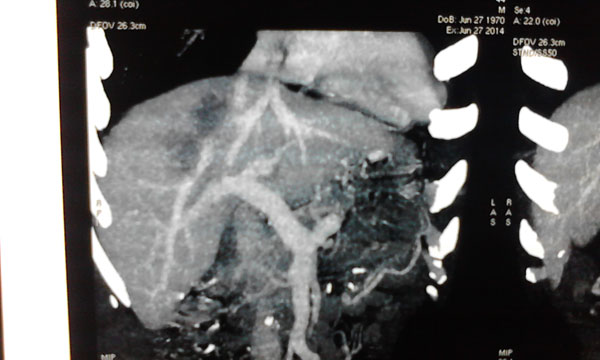

肿瘤与肝静脉